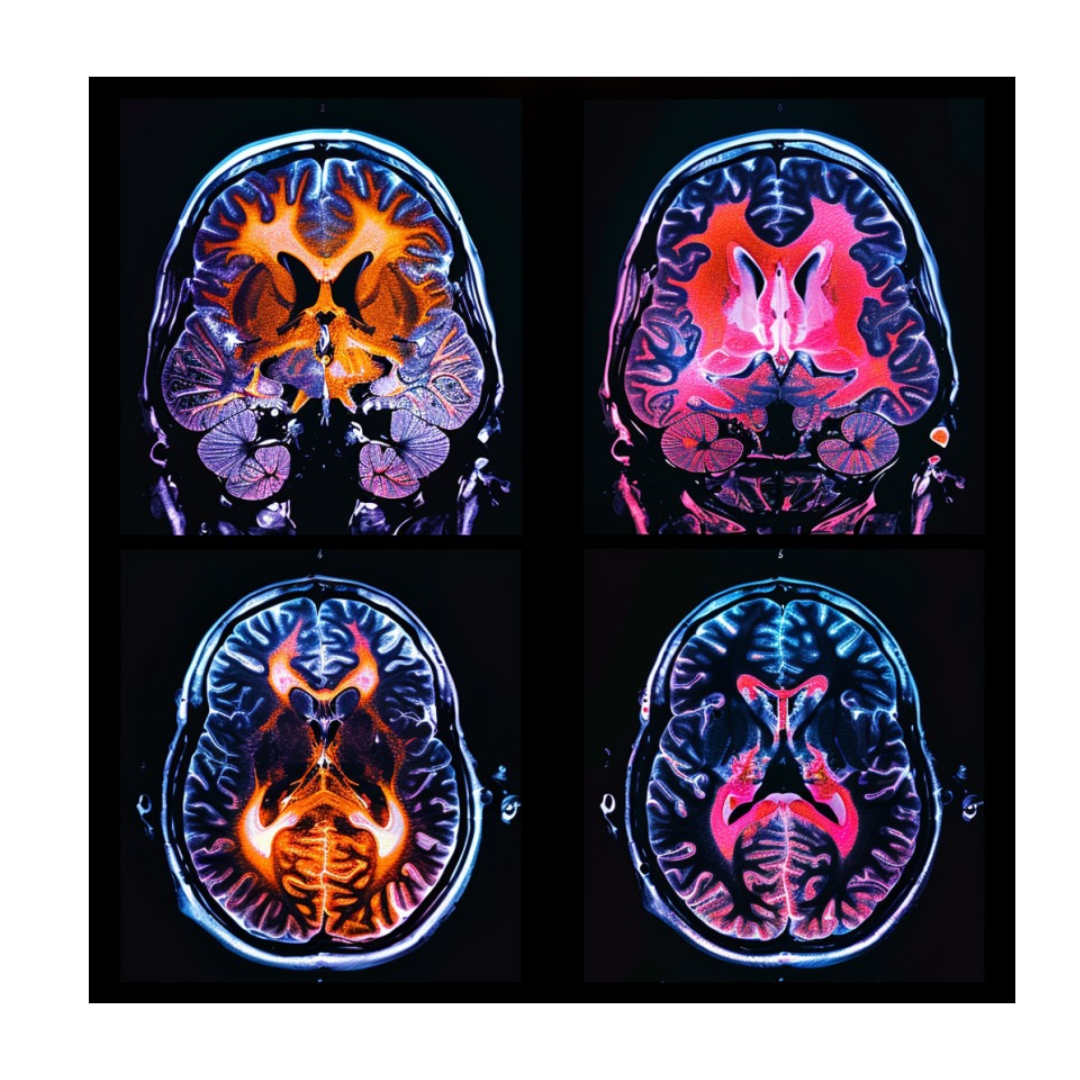

세 번째, 영상 검사가 필요할 때도 있습니다.

뇌 자기 공명영상(MRI)이나 양전자방출단층촬영(PET)을 통해 뇌의 구조적 변화를 확인할 수 있습니다. 이런 검사는 다른 신경계 질환과의 감별 진단에 중요한 역할을 합니다.

환자들은 이 과정에서 때로는 기계의 소음과 밀폐된 공간에 불안감을 느끼기도 합니다. 그렇지만, 정확한 진단을 위해 꼭 필요한 과정이라는 점을 이해하고, 의료진의 지시에 따라 차분히 검사를 받아야 합니다.